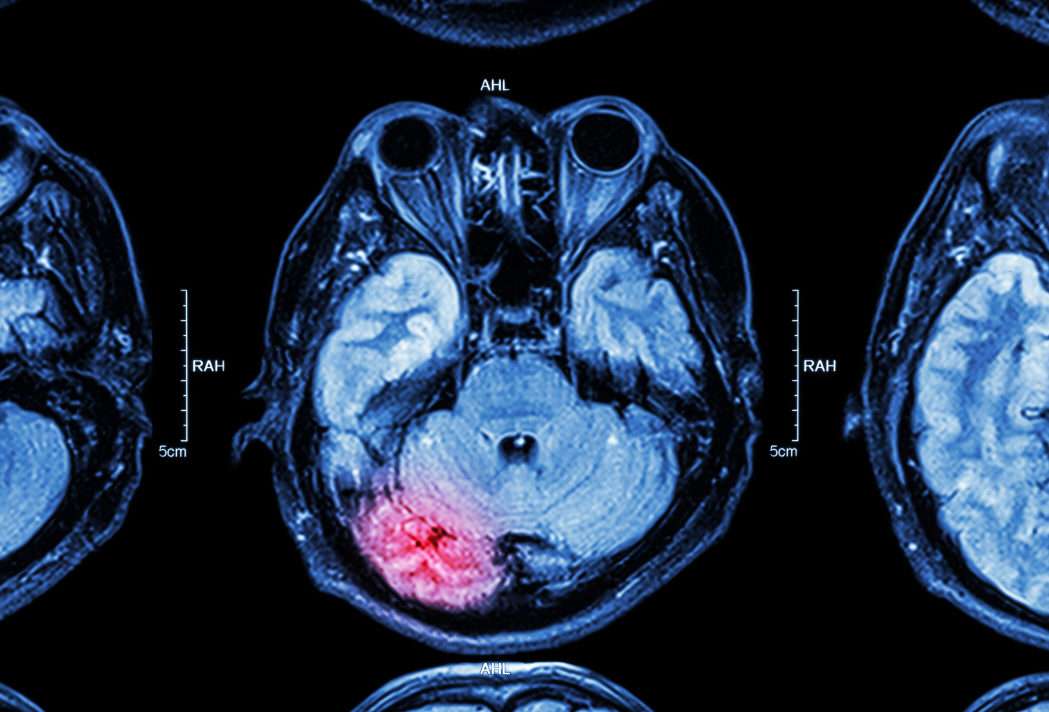

The brain is the control centre for most of your body’s vital functions. Even a minor injury can have serious, lasting effects and lead to a substantial compensation pay-out. Starting a compensation claim may well be the best chance of securing the amount of care you may need for the rest of your life. Whilst the NHS has an obligation to provide a certain level of care, it is rarely enough and places the whole family under avoidable stress and financial pressure